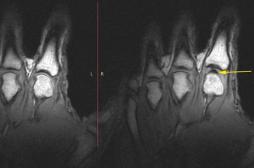

LES MALADIES

J'AI MAL